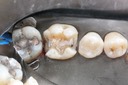

Alan Chinn #3 pre-op

Alan Chinn #3 caries removal 2

Alan Chinn #3 prep

Alan Chinn #3 finish